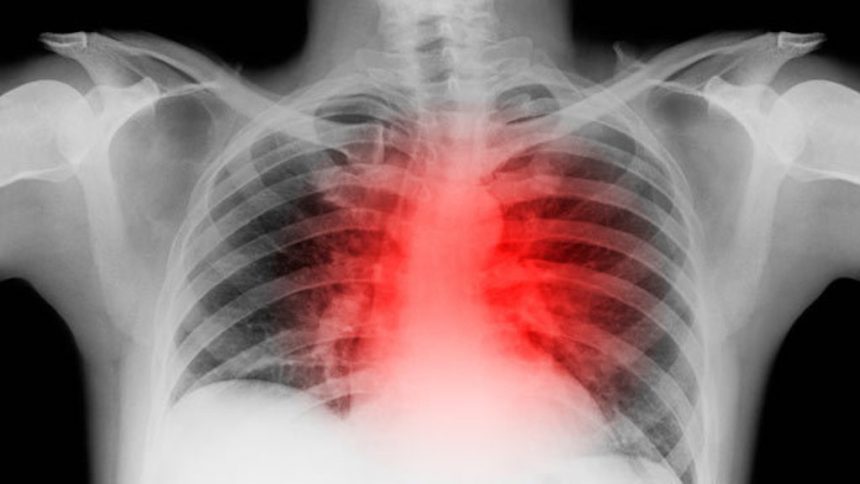

Viroza pulmonară sau viroza respiratorie este o infecție acută virală ușoară și autolimitata a tractului respirator superioar care determină simptome variabile de tip strănut, nas înfundat, secreții nazale, gât iritat, febră mica și dureri de cap.